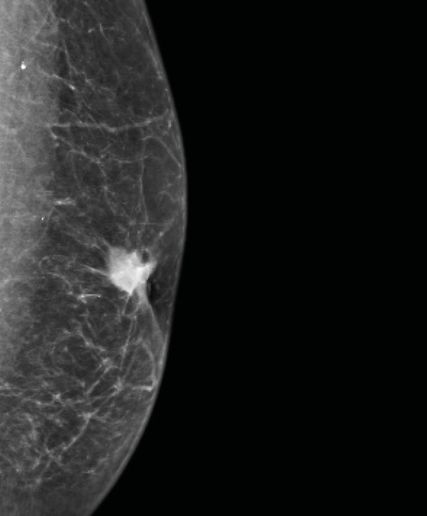

Prof. Exner befasste sich mit einem bei Ärzt:innen, Männern und der Bevölkerung allgemein noch immer wenig präsenten Thema: dem Brustkrebs beim Mann. Etwa 0,5–1% der Mammakarzinome betreffen Männer. Risikofaktoren sind vor allem höheres Alter, Rauchen, Alkoholabusus, Adipositas und eine genetische Disposition (v.a. BRCA1/2-Mutationen).1 Aufgrund des geringen Bewusstseins für die Krankheit erfolge die Diagnose meist erst spät (Abb.1). Zu diesem Zeitpunkt lägen in 30–40% der Fälle bereits Lymphknotenmetastasen vor, erklärte Exner. Diagnostik, Therapie und Nachsorge entsprechen den Maßnahmen bei postmenopausalen Frauen.1,2 Doch es gibt auch Unterschiede. So liegt beim Mann häufiger eine genetische Disposition vor und das Risiko für Zweitmalignome ist bis zu 20% höher als bei der Frau.1 Mehr als 90% der Männer hätten ein ER-positives, invasiv-duktales Karzinom,1 das sich meist als derber Tumor hinter der Brustwarze zeige (Abb.2), sagte Exner. Allerdings kämen auch andere Tumoren vor, etwa Sarkome.

Abb. 1: Wie bei diesem Patienten wird ein Mammakarzinom bei Männern meist erst in einem fortgeschrittenen Stadium diagnostiziert